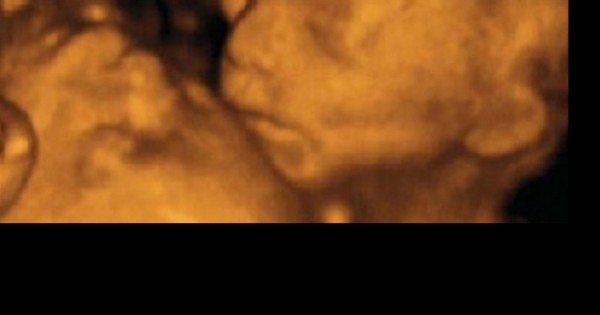

למרבה הצער, הסיפור הטרגי הזה הוא לא מאוד נדיר במקרה של תאומים. עם זאת, במקרה של משפחת מקלנטייר הוא טומן בחובו גם איזושהי נקודת אור מנחמת: בצילומי האולטרסאונד שעשו לעוברים, נדהמו הרופאים לגלות שלמרות הבדלי המשקל והגודל הנכרים בין שני התאומים (הזכר שוקל 255 גרם בלבד, שליש מאחותו), השניים צולמו כשהם מחזיקים ידיים.